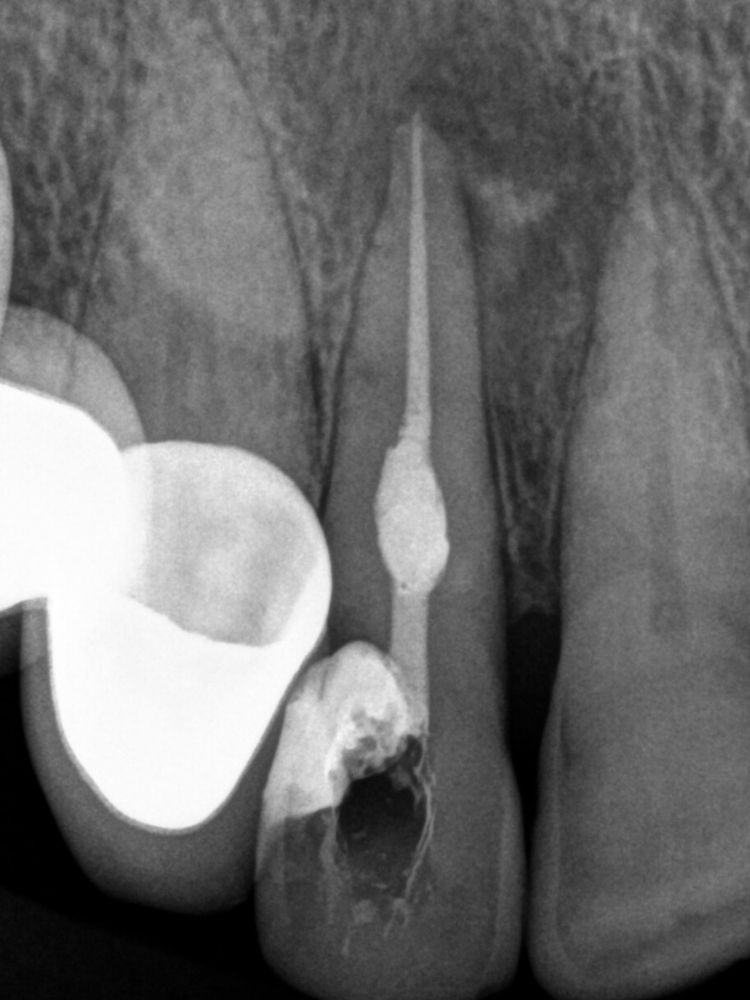

En una segunda cita pasamos al siguiente peldaño del tratamiento. Procedimos a retirar todos los materiales intraconducto y obturar. Para ello, en primer lugar, se realiza el Downpack con System B para sellar el tercio apical. A continuación, con la técnica de inyección de gutapercha, se rellena el tercio medio y coronal del conducto de la pieza 1.2, con el consiguiente sellado de la cavidad de la reabsorción.

Para el éxito de este tratamiento de endodoncia con reabsorción interna es fundamental el uso de la gutapercha termoplástica. Con ello, somos capaces de obturar. Un ejemplo de cómo, pese a no tener en su historial unos antecedentes marcados que pudieran hacer prever este problema, unas molestias y las revisiones periódicas pueden ayudar a detectar una problemática a tiempo de resolverla antes de que vaya a más.